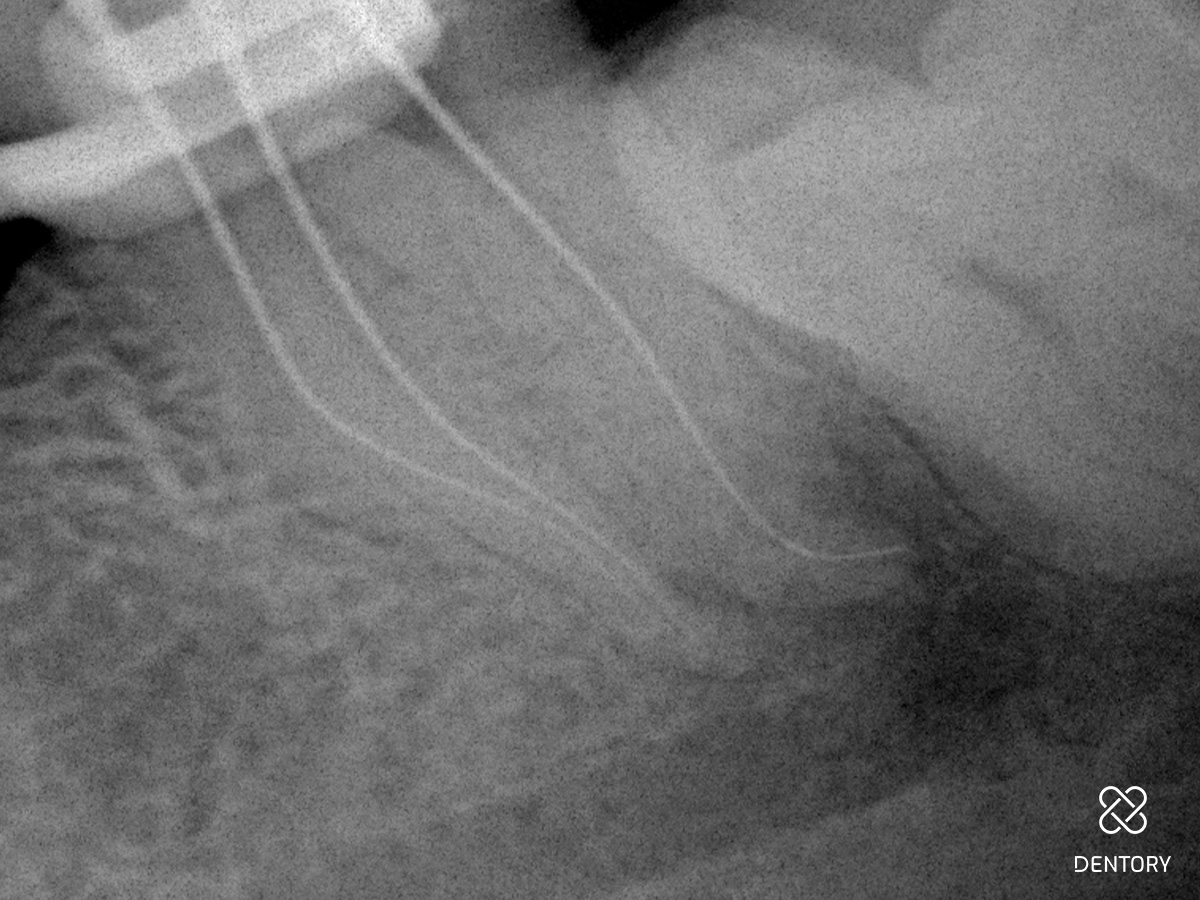

Abbildung 1

Diagnoseaufnahme (alio loco) Regio 37: Symptomatische apikale Parodontitis (PAI 4). Als Besonderheit erkennt man bereits die S-förmige Kanalkrümmung in der mesialen Wurzel und die J-förmige apikale Krümmung im distalen Kanal.